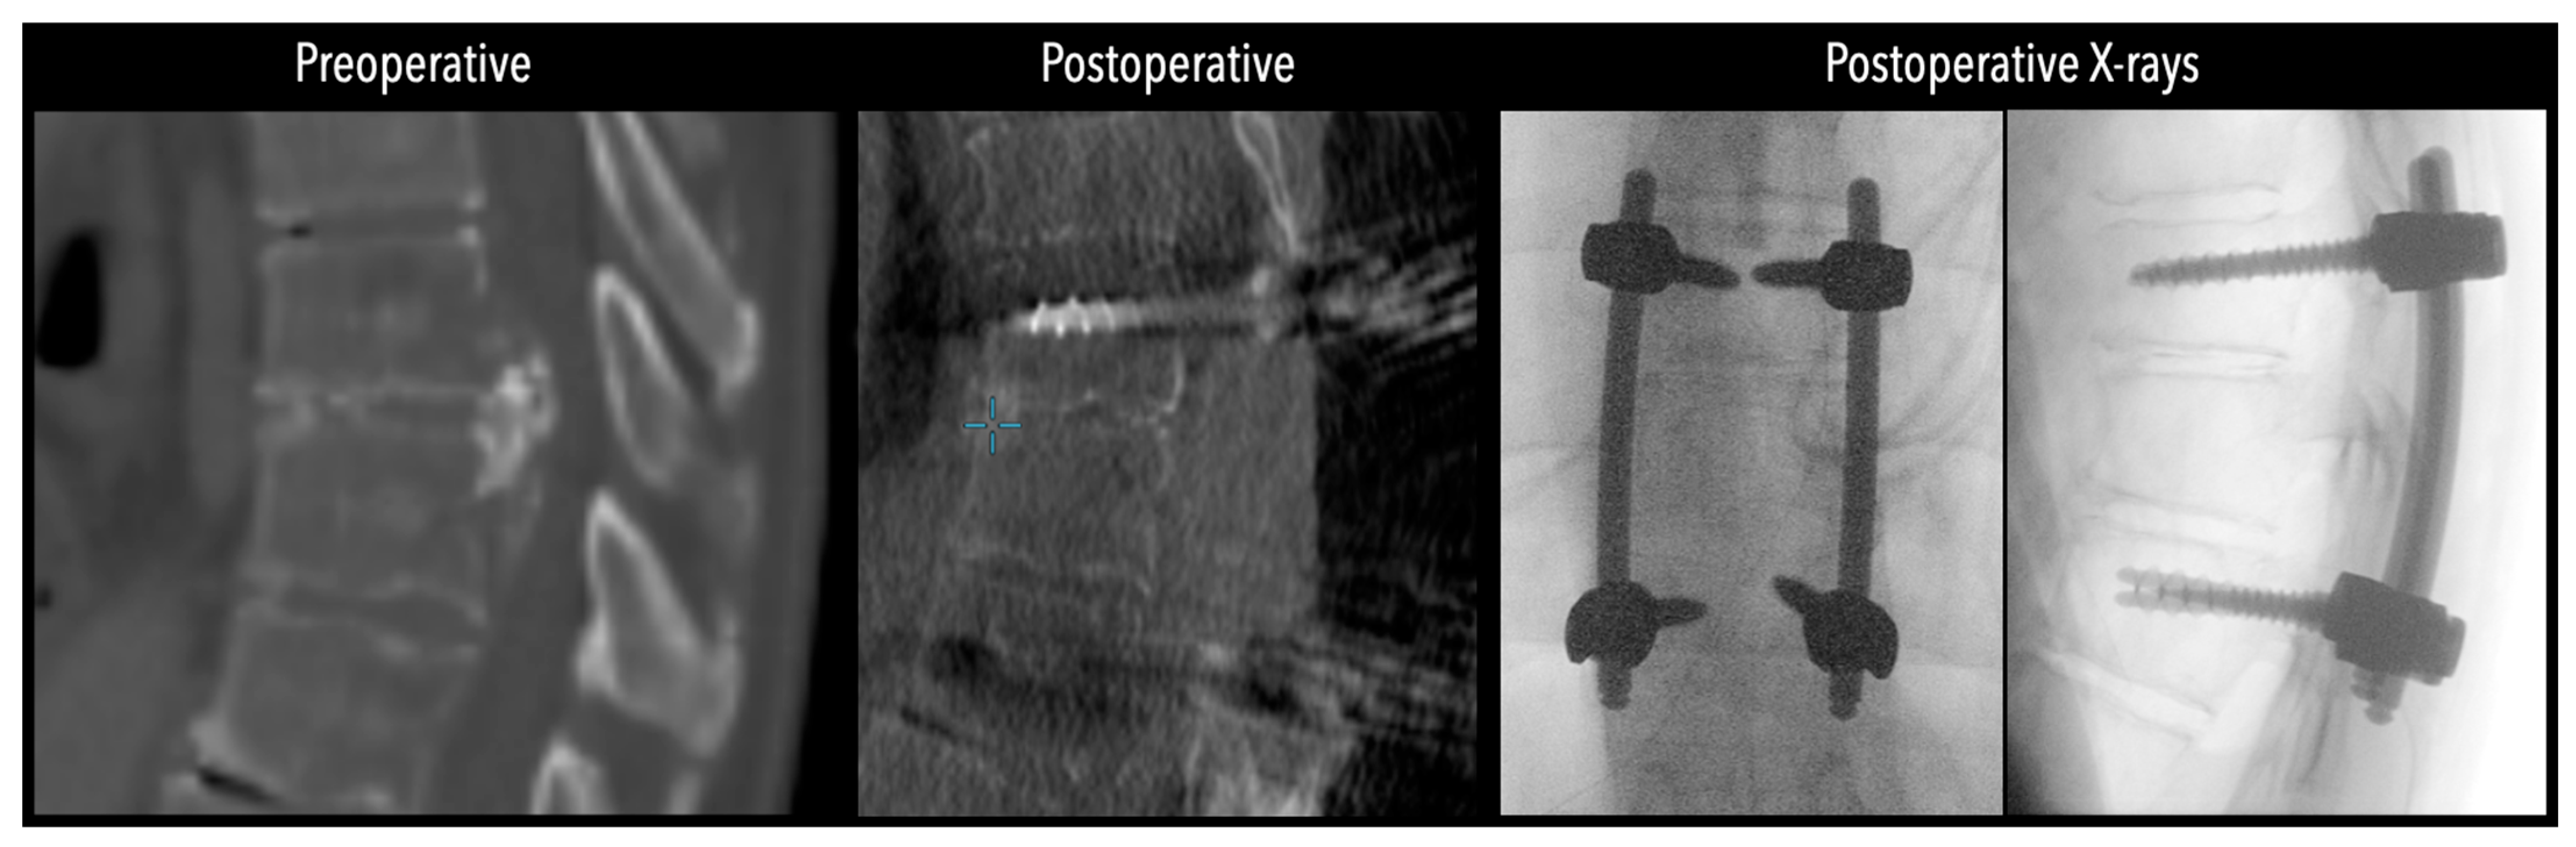

In three of the seven cases, the exiting nerve root at the level of the herniation was ligated due to poor visualization and transected extradurally to improve access. In the remaining four patients, the nerve root was either preserved or dissected intradurally using isocool bipolar diathermy and microsurgical scissors. With gentle medial retraction of the cord under gravity and protection using a micro-patty, the calcified disc was exposed. The ventral dura, when intact, was incised sharply and dissected from the disc surface where possible (Figure 2a,b and Figure 3). Disc removal was performed using a hockey-stick-shaped Misonix bone scalpel with constant irrigation, guided by intraoperative neuronavigation. The disc material was resected to a depth of 1–2 mm beyond the posterior vertebral wall to ensure adequate decompression. A second O-Arm spin was routinely performed following discectomy to confirm satisfactory decompression, especially given the limitations of the postoperative MRI due to the metal artefact (Figure 4, Figure 5 and Figure 6).

Figure 4. Comparative pre- and postoperative CT scans for two different patients (left and right), illustrating complete discectomy.

Figure 5. Left side: Comparative pre- and postoperative CT scan of a patient, illustrating complete discectomy. Right side: Postoperative X-rays illustrating fixation.